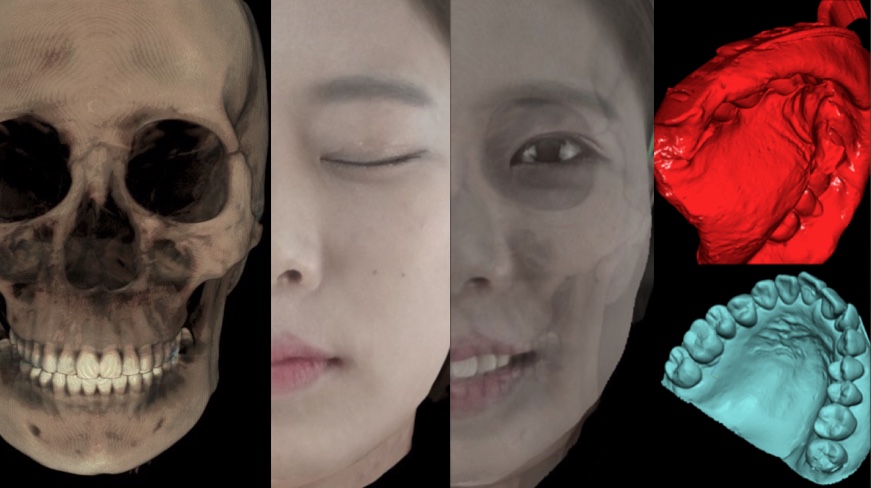

R2STUDIO: ONE STEP collection & digitization of patient data within 10 min (CBCT + 3D facial scan + STL dentition file)

R2STUDIO digital work flow

Step01

Data Collection

- CBCT

- Face scan

- Impression scan

Collect all patient’s data less than 10 minutes

Complete CBCT, Smile, impression scan, less than 10 minutes and create the digital virtual patient.